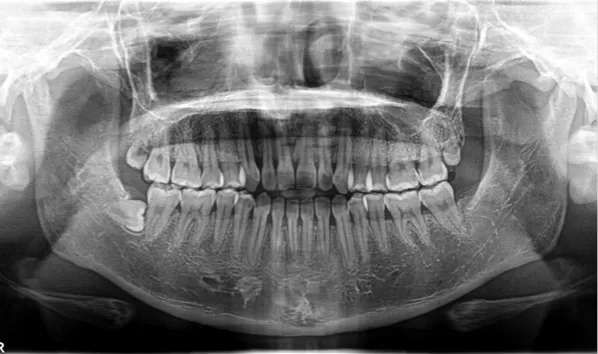

X-rays before treatment

[Panoramic Radiography/Lateral Cephalogram]